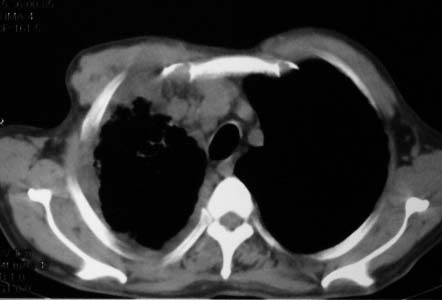

影象表现:右肺上叶大片状、网格状及索条致密影,蜂窝影,其内参杂斑点状小结节,密度不均匀,内见含气支气管像,纵隔内见肿大淋巴结.

右肺上叶见大片状及索条致密影,密度不均,内见含气支气管症,纵隔内见肿大淋巴结.

影象表现:右肺上叶大片状、网格状及索条致密影,蜂窝影,其内参杂斑点状小结节,密度不均匀,内见枯枝样含气支气管像,纵隔内见肿大淋巴结.胸膜广泛增厚,前胸壁似受累.少量胸腔积液.纵隔内淋巴结的直径>1.5cm.右侧胸廓体积缩小.考虑:1 肺结核合并间质纤维化 2 细支气管肺泡癌

右肺上叶大片状、网格状及索条致密影,蜂窝影,其内参杂斑点状小结节,密度不均匀,内见枯枝样含气支气管像,纵隔内见肿大淋巴结.胸膜广泛增厚,前胸壁受累增厚.少量胸腔积液.纵隔内淋巴结的直径>1.5cm.右侧胸廓体积缩小.考虑: 细支气管肺泡癌并肺内癌性淋巴管炎。